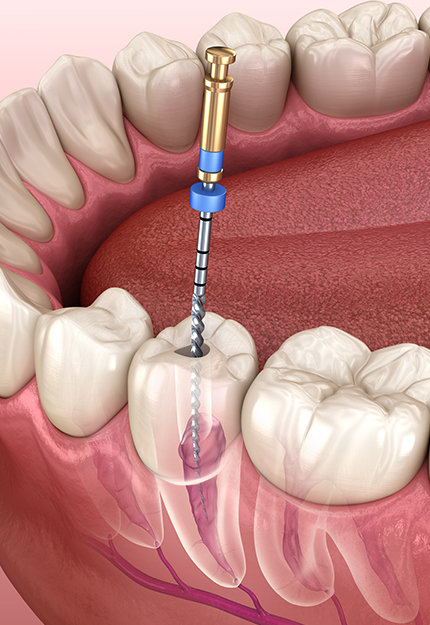

- 일반진료

자연치아 보존을 최우선으로 한

기본에 충실한 진료 - READ MORE

- 상악동 거상술+근관치료

- 상·하악 임플란트+근관치료

- 상악동 골이식+근관치료

- 구치부 근관치료+상악동 골이식